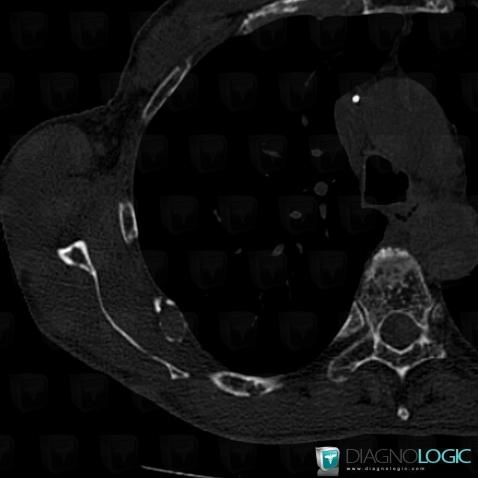

Multiple myeloma, Ribs, CT

Here is the specific information in the key image above:

- Diagnosis Multiple myeloma, Location(s) Ribs, with gamuts Osteolytic lesion of ribs